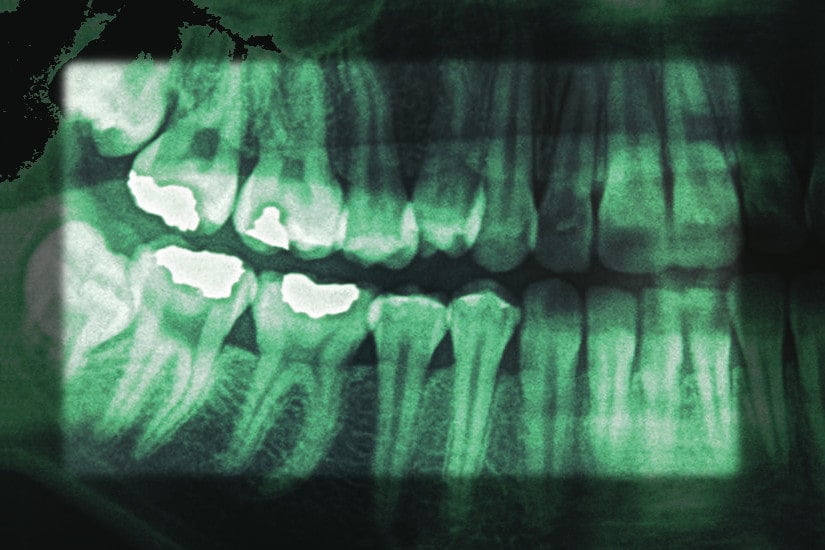

Dental X-rays, also known as radiographs, are essential diagnostic tools in dentistry, providing detailed images of teeth, jaws, and surrounding structures invisible during a standard oral exam. With over 90% of U.S. dentists using X-rays annually to detect issues like cavities and bone loss, per the American Dental Association (ADA), these images are critical for early diagnosis and effective treatment. By revealing hidden dental conditions, X-rays enable proactive care, preserving oral health and radiant smiles. This article explores the importance, types, applications, safety, challenges, and future trends of dental X-rays, highlighting their pivotal role in modern dentistry.

Dental X-rays provide a comprehensive view of oral structures, uncovering issues not visible to the naked eye. They detect cavities, bone loss, tooth root abnormalities, and impacted teeth, which affect 26% and 50% of U.S. adults for decay and gum disease, respectively, according to the CDC. By identifying problems early, X-rays prevent complications like tooth loss or severe infections, reducing treatment costs by up to 50%. Used in routine check-ups, orthodontic planning, and surgical preparation, X-rays are indispensable for personalized dental care, ensuring both functional and aesthetic outcomes.

• Bitewing X-Rays: Capture upper and lower back teeth, showing crowns and bone height to detect interdental cavities and early bone loss. Common in routine exams, used every 1–2 years.

• Periapical X-Rays: Image the entire tooth (crown to root) and surrounding bone, identifying root infections, abscesses, or structural damage. Ideal for targeted assessments.

• Panoramic X-Rays: Provide a broad view of the entire mouth, including jaws, teeth, sinuses, and temporomandibular joints (TMJ), used for orthodontics or wisdom teeth evaluation every 3–5 years.